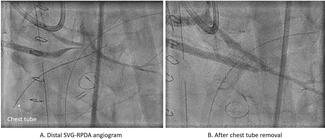

Tak-Shun Chung, MD, MBBS; Sui-Fung Wong, MBChB; Hiu-Cheong Chow, MBBS

A 75-year-old man was admitted for non-ST-segment elevation myocardial infarction. Coronary angiography showed focal severe disease at obtuse marginal artery and severe medina 1,1,1 bifurcation disease involving proximal to middle left...

02/13/2024